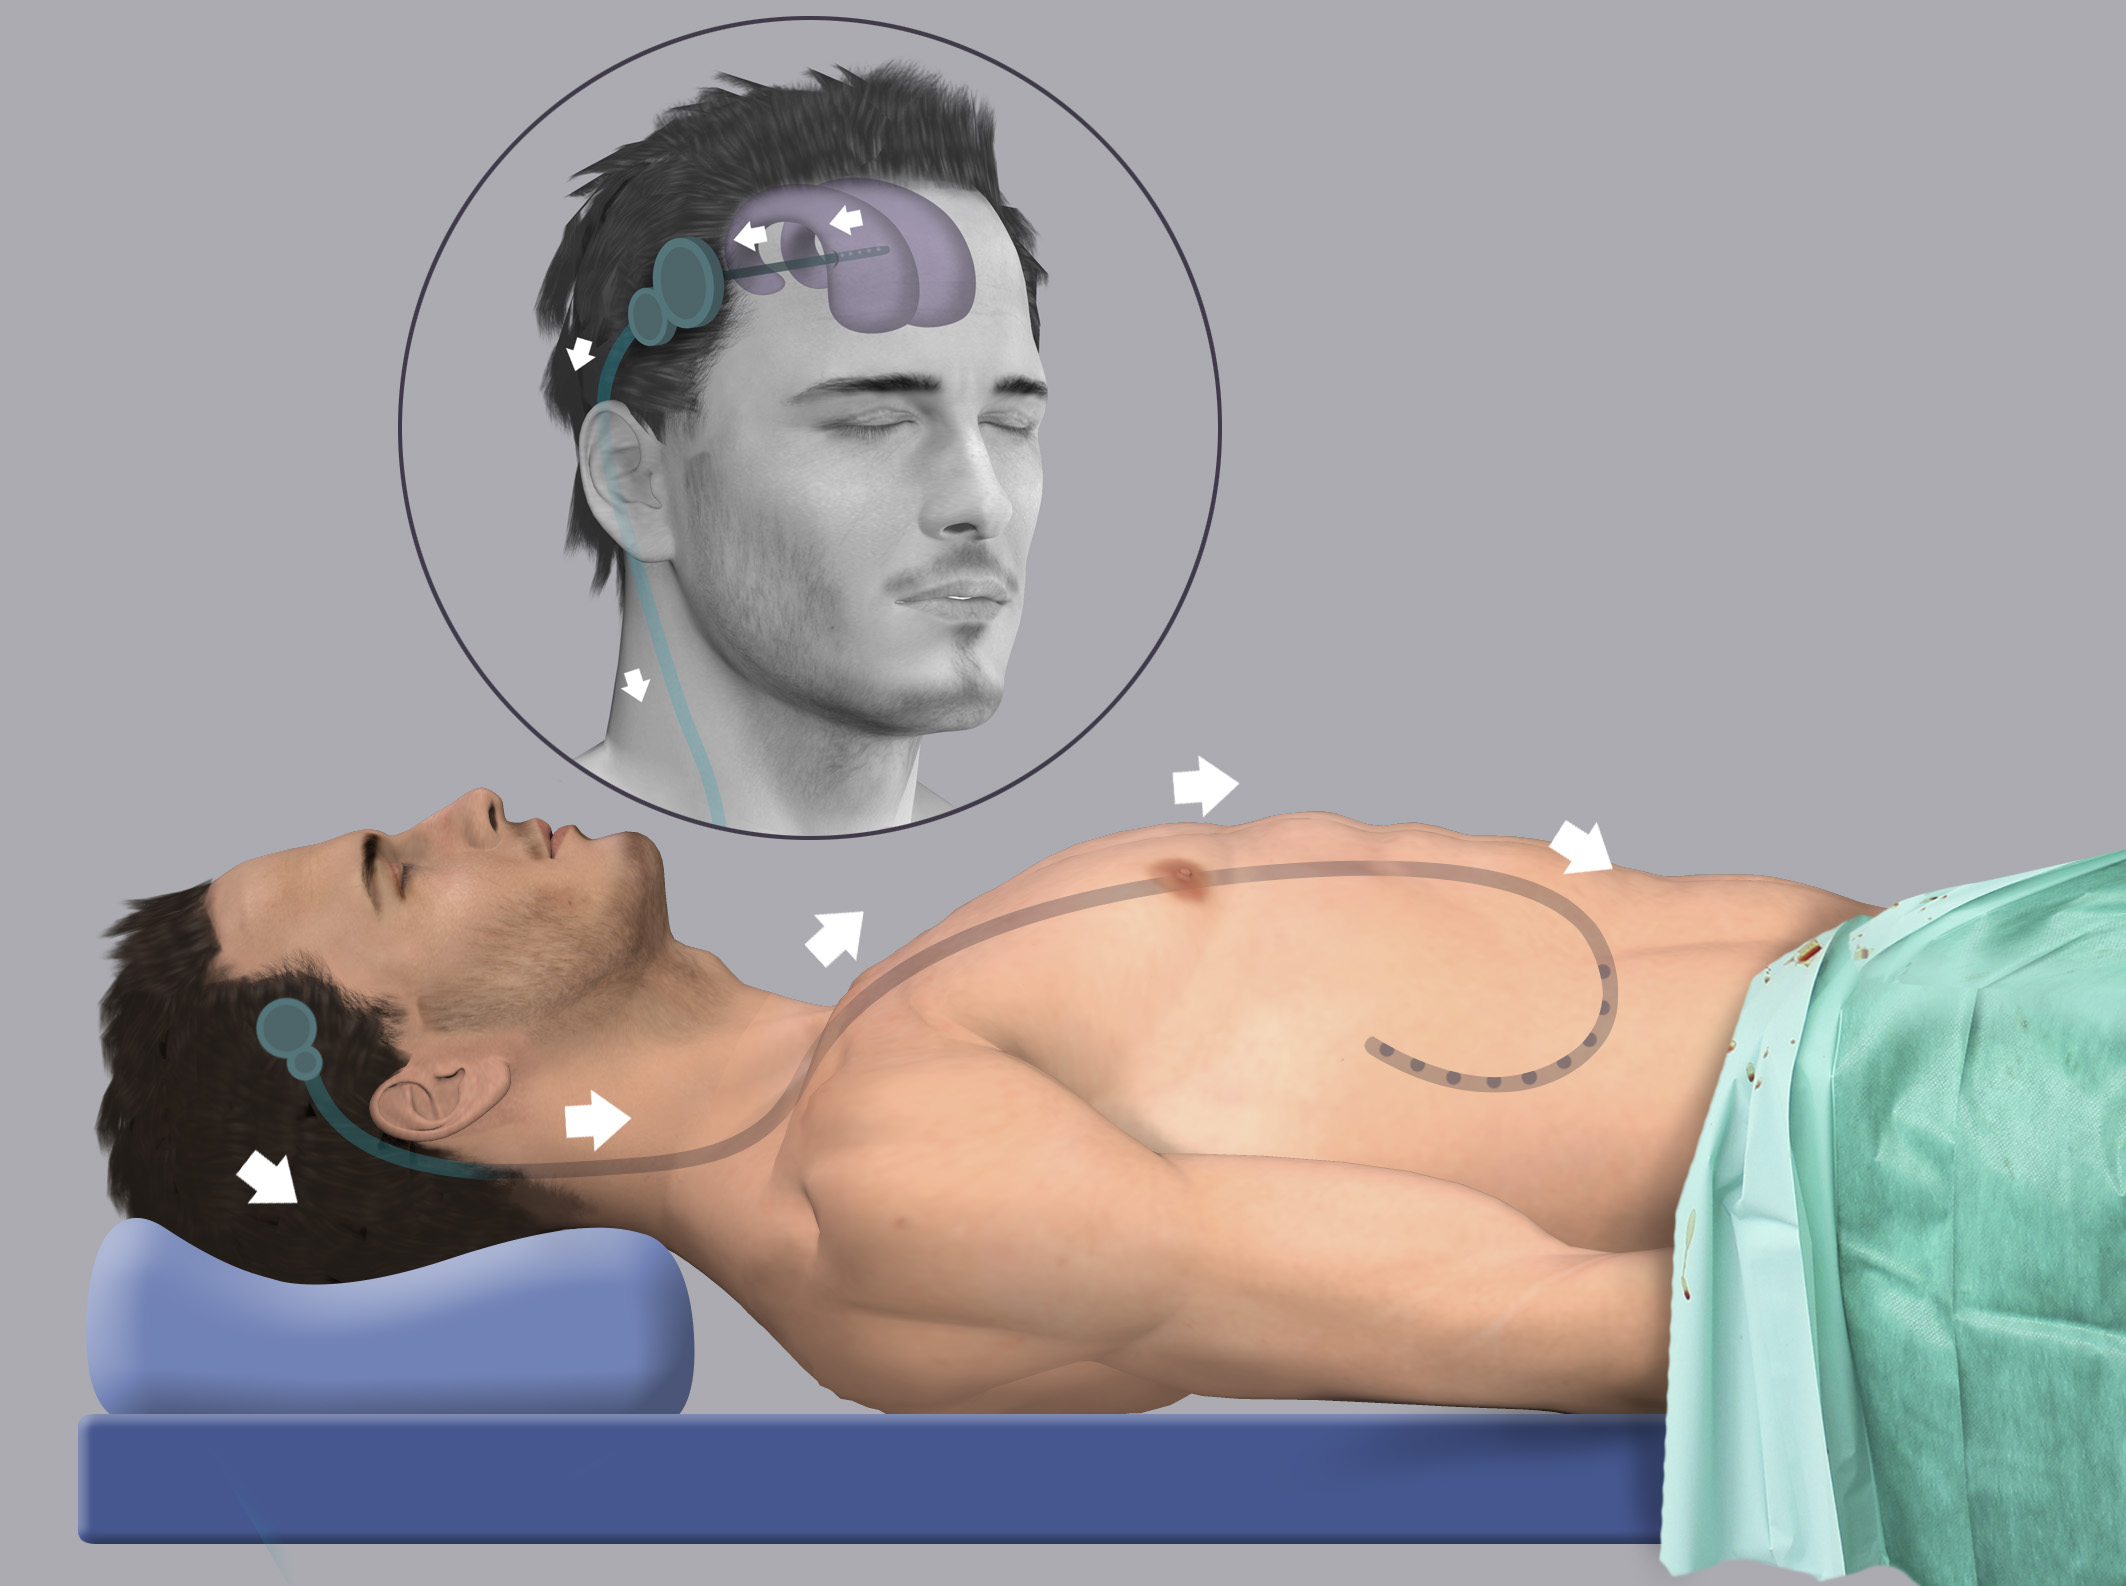

Вентрикуло-перитонеальный шунт: Показания и применение

Раздел: Фотоальбом решений